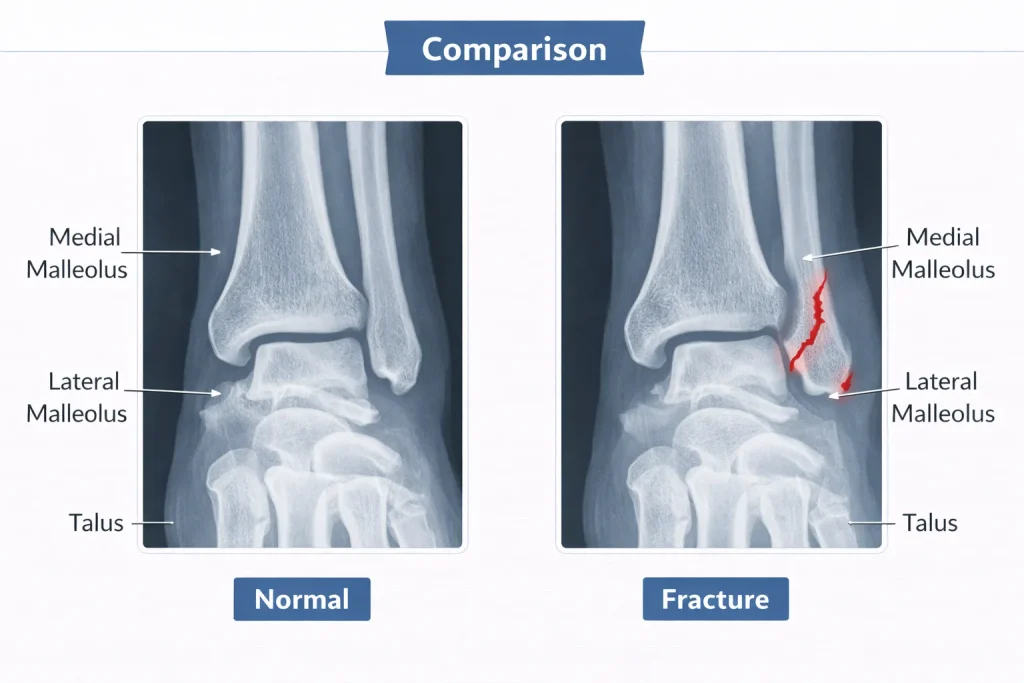

An ankle fracture refers to a break in one or more bones forming the ankle joint. The joint is composed of:

The bony prominences felt on either side of the ankle are called malleoli:

- Medial malleolus (inner side)

- Lateral malleolus (outer side)

- Posterior malleolus (back part of tibia)

An ankle fracture may involve one, two, or all three malleoli. The severity depends not only on the bone break but also on ligament damage and joint stability.